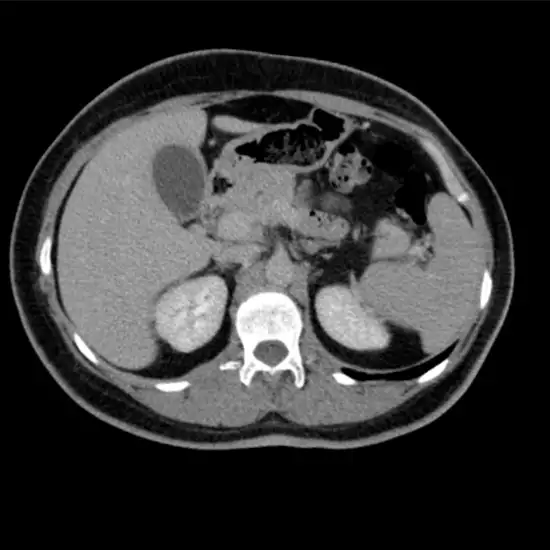

CECT (Contrast Enhanced Computed Tomography) Triple Phase Upper Abdomen is an imaging procedure that provides cross-sectional images of organs of abdominal structure. The abdominal structure is inclusive of various organs such as the liver, kidney, pancreas, spleen, Gastrointestinal tract (GI Tract) and their surrounding area. For this scan, contrast media is used to highlight the abdominal structure and to obtain a clear image.

CECT (Contrast-enhanced Computed Tomography) screening of the Triple Phase Upper Abdomen is a non-invasive radiology test used to provide cross-sectional images of organs of abdominal structure and surrounding tissue. CECT Triple Phase Upper Abdomen is done to look for the conditions of the upper abdomen and the surrounding area.